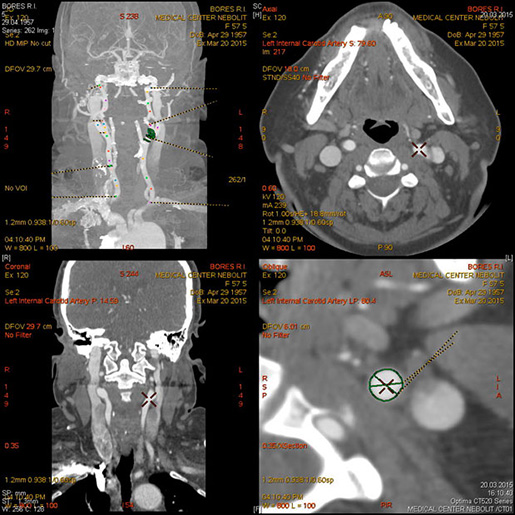

МСКТ-ангиография сосудов головного мозга

МСКТ высоко чувствительна в диагностике атеросклеротических кальцинированных, ,,мягких,, бляшек. В большинстве клиник метод МСКТ стал основным методом диагностики заболеваний сосудов сонных артерий, грудной, бюшной аорты, периферических пртерий.

Показания:

- диагностика сосудистых заболеваний (аневризмы, стенозы, мальформации, аномалии развития)

- Выявление венозного тромбоза

- Подозрение на острое кровотечение